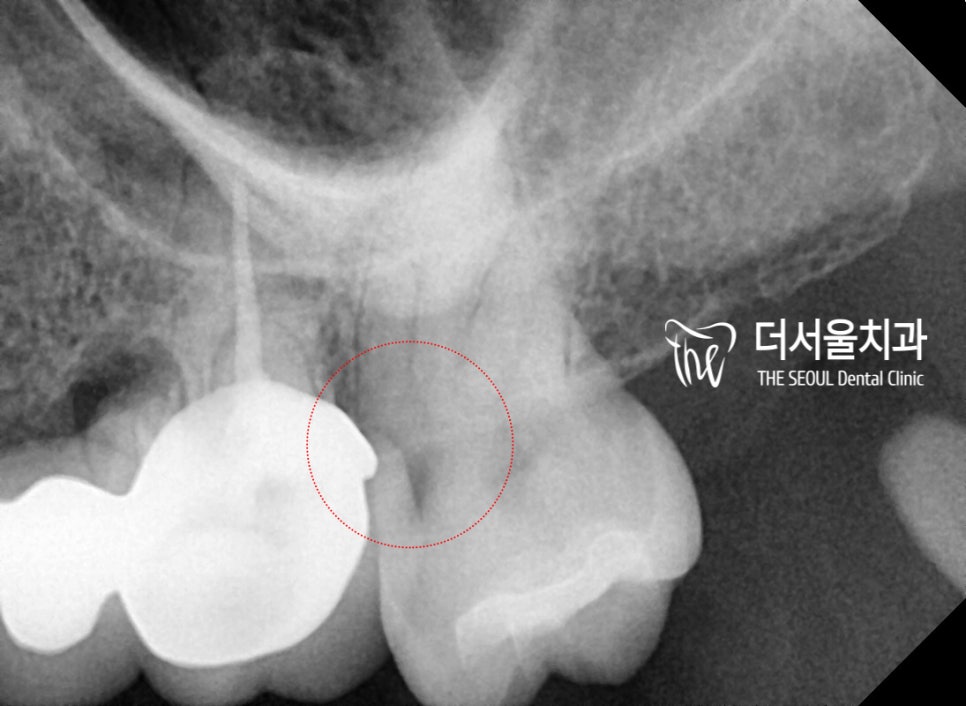

먼저 엑스레이 한장을 같이 볼게요.

표시를 2군데에 해놨습니다.

화살표를 쳐 둔 곳은,

인접면 우식증이 있는 곳이고

그 바로 앞에 있는 빨간색으로

각도를 표시 해 둔 곳은 크라운의

외형을 찍어둔 곳입니다.

예상컨데, 인접면 우식증이

나타난 이유는 바로 앞에 있는

크라운의 형태와도 연관을

지을 수 있기 때문에 이렇게

표시를 해두었습니다.

보통, 크라운의 외형 및

치아와 맞닿는 마진의 형태는

턱이지거나 이행되는 면이

활택해야 정상입니다.

면이 울퉁불퉁하거나 또는

면이 활택하지 못했을 경우에는

음식의 저류(음식물이 쉽게 낀다는 뜻)에

따라서 쉽게 충치들이 발생 될 수 있죠.

근데 방사선 사진을 찍어서 보면,

충치의 범위 및 위치가 확인이 되며

신경과 가까이 근접해 있기 때문에

신경치료를 할 수 밖에 없는

상황이라는 것을 알 수 있습니다.